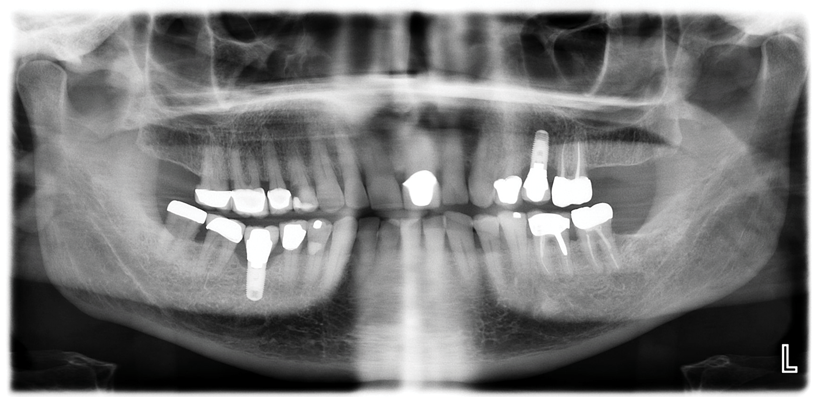

The patient's radiographic assessment, performed immediately following the initial clinical evaluation, included a panoramic radiograph (Figure 4) and bitewing and periapical radiographs of No. 30 (Figure 5). Panoramic findings showed generalized horizontal bone loss confined to the coronal third (15% to 20%), with circumferential bone loss, also referred to as "cupping," around both of the patient's implants, Nos. 30 and 13.

Fig 4. Panoramic radiograph. Both implants (Nos. 13 and 30) demonstrated similar horizontal bone loss confined to the coronal one-third.

Figure 4